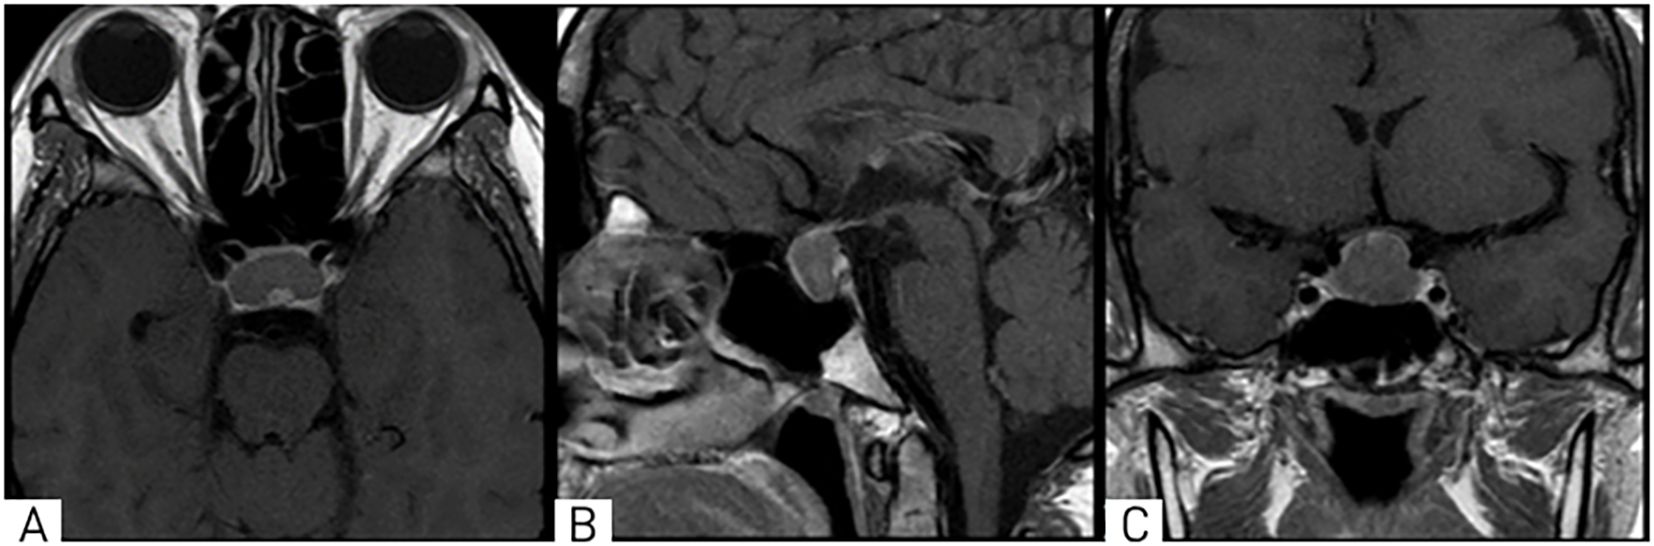

A 28-year-old female patient presented to the National Center for Neurosurgery with complaints of headaches, decreased visual acuity, infertility for 4 years, and menstrual irregularities (amenorrhea). An ophthalmologist consultation revealed the following diagnoses: OU - papilledema, OU - peripheral and central chorioretinal degeneration, OU - mild myopia, OU - retinal vascular angiopathy, and OU - ocular hypertension. Brain MRI (Magnetic Resonance Imaging) with contrast was recommended. MRI revealed a mass in the chiasmal-sellar region with predominantly endosupra-sellar and minor lateral-sellar growth (Figure 1).

Figure 1. On MRI, T1-weighted images in axial (A), sagittal (B), and coronal (C) projections show a well-defined mass in the chiasmal-sellar region with predominantly endosupra-laterosellar growth, compressing the optic chiasm.